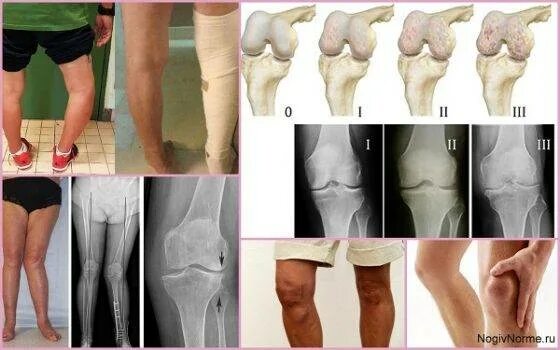

Деформирующий остеоартроз коленного сустава 1